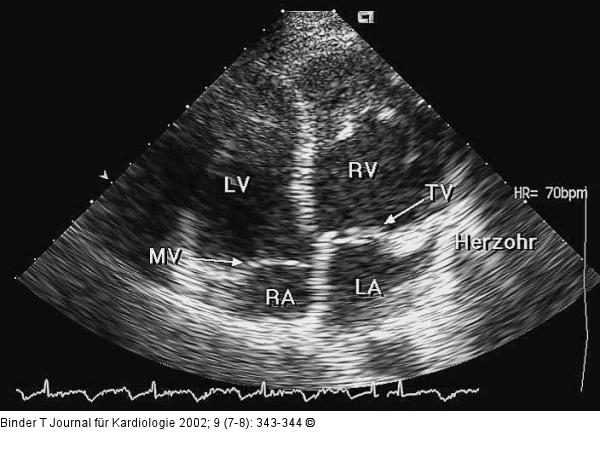

Abbildung 2: Kongenital korrigierte Transposition der großen Gefäße (ccTGA) Vierkammerblick: Die linksseitig gelegene AV-Klappe (morphologisch Trikuspidalklappe, TV) inseriert weiter apikal als die rechtsseitige AV-Klappe (morphologisch Mitralklappe, MV): die typische Dreiecksform des linken Herzohrs charakterisiert den linken Vorhof (LA); LV = (morphologisch) linker Ventrikel, RA = rechter Vorhof, RV = (morphologisch) rechter Ventrikel. |